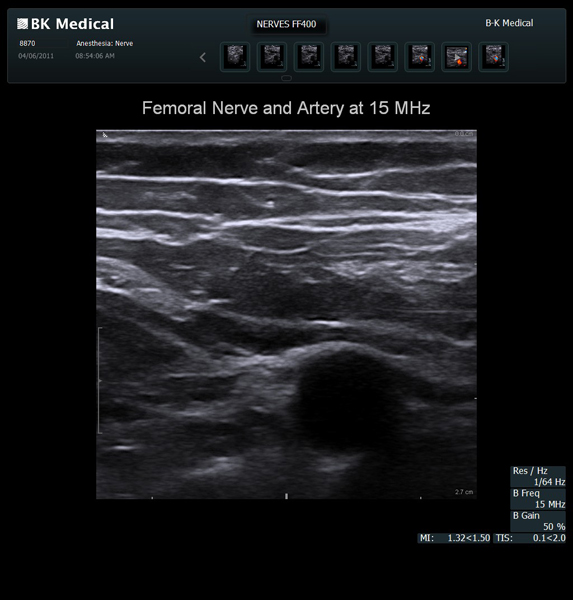

The Flex Focus 400 exp ultrasound system offers premium image quality with fast frame rates for excellent temporal resolution. The system features Automatic Mode Adjustment (AMA) to optimize high resolution B-Mode Imaging when changing modes and depth.

Transducers Designed for Guidance

BK Medical offers high-frequency linear transducers, imaging from 18-2 MHz for upper and lower extremities, and curved array abdominal transducer 8820e for special deep nerves or paravertebral/spinal applications. Our transducers provide superb detail that makes it easy to see your needle during procedures.